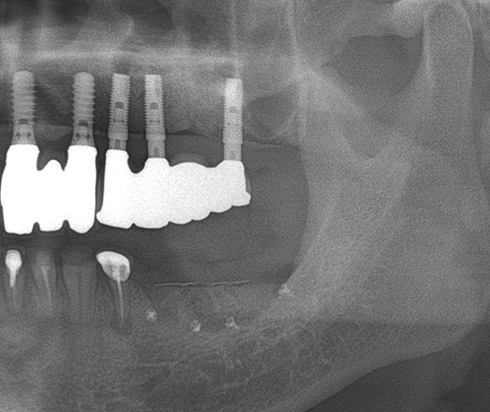

Another clinical case using non resorbable membrane and bone tac

• Another clinical case using  non resorbable membrane and bone tac 1